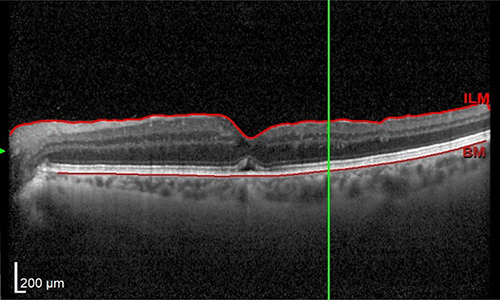

La diagnosi si basa su una visita oculistica completa e su un esame semplice, rapido e molto preciso: l’OCT.

L’OCT esegue una scansione della retina, simile a una TAC ma senza radiazioni, utilizzando solo raggi infrarossi. Questo permette di visualizzare il foro maculare e di misurarne con precisione le dimensioni.